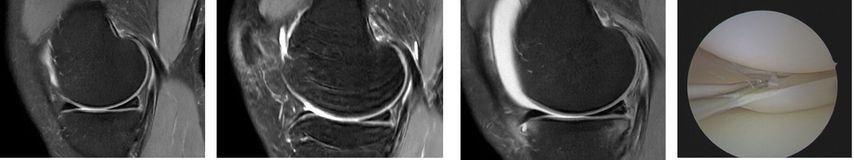

Behrendt stellte im Zuge seines Vortrags den Fall einer 25 Jahre alten Handballspielerin mit Distorsionstrauma im Mai 2023 vor. Bei einer MR-gestützten Partialruptur des vorderen Kreuzbandes mit geringer subjektiver Instabilität wurde zunächst konservativ behandelt. Im Verlauf zeigten sich jedoch zunehmende Hyperintensität am Innenmeniskus-Hinterhorn und eine Restinstabilität beim Handballspielen. Ein Jahr nach dem Unfall führte die zunehmende Symptomatik zu einem klaren Meniskusriss, sodass eine Kreuzbandersatzplastik und eine Rekonstruktion des Innenmeniskusrisses durchgeführt wurden (Abb.1). Diese Fallvignette verdeutlicht, dass nach unzureichender Versorgung eines vorderen Kreuzbandrisses das Risiko für zusätzliche Meniskus- und Knorpelschäden hoch ist. Eine Metaanalyse zeigte, dass dies in 88 % der Studien (35 von 44) auftrat. Kritische Zeitgrenzen lagen bei sechs Monaten für Meniskus- und zwölf Monaten für Knorpelschäden; danach stieg die Wahrscheinlichkeit weiterer Schädigungen deutlich an. Mit zunehmendem zeitlichem Abstand zum Kreuzbandriss verschlechtert sich zudem die Rekonstruierbarkeit der Menisken.8

Dies verdeutlicht der Fall einer 46 Jahre alten Patientin mit atraumatischen Schmerzen im medialen Kniegelenk links (Abb. 2). In der präoperativen MRT-Diagnostik zeigt sich der degenerative Innenmeniskuswurzelriss (linkes Bild, Pfeil). In der präoperativen Röntgen-Ganzbeinaufnahme im Stehen ist ein Varus-Malalignment von 4° zu erkennen (Bilder in der Mitte). Es erfolgte eine arthroskopische Innenmeniskuswurzelrefixation mittels transtibialer Auszugsnaht, kombiniert mit einer valgisierenden medial öffnenden hohen tibialen Osteotomie (rechts).